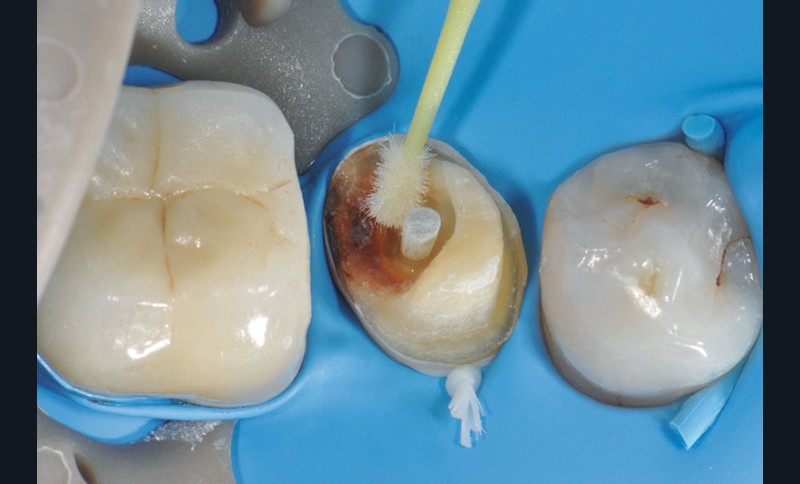

3, 4, 5. La restauration est déposée, les tissus carieux éliminés et la cavité d’accès aménagée avant la réalisation du traitement endodontique. La radiographie postopératoire permet de visualiser l’obturation du canal latéral en regard de la LIPOE.